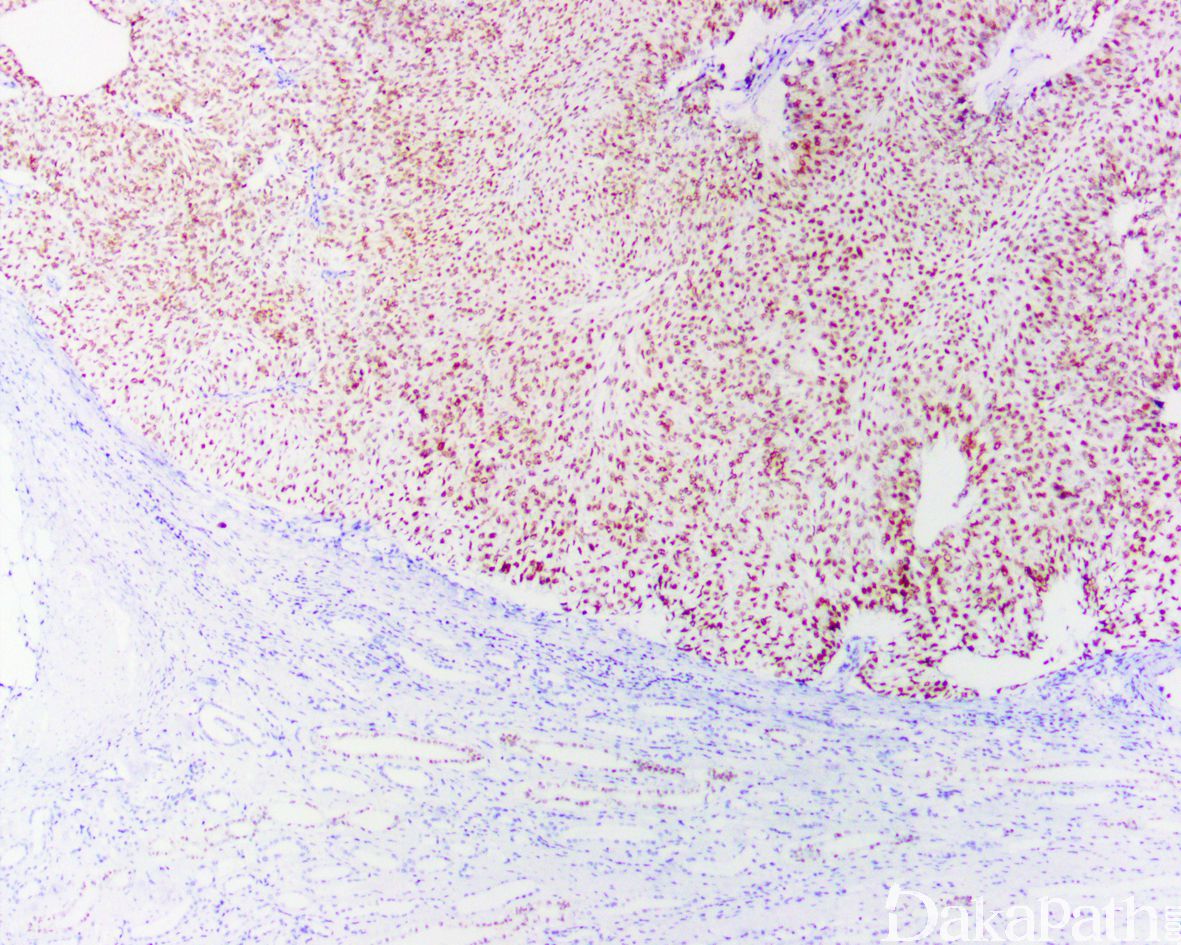

Low Grade Non-Invasive Papillary Urothelial Carcinoma

非浸润性低级别尿路上皮乳头状癌由纤细的乳头状结构组成,常见乳头分支和融合,被覆上皮层次增加。核轻度增大,可见空泡状染色质,常见核仁,核分裂可见于上皮的任何层次

镜下肿瘤由纤细的乳头状结构组成,常见乳头分支和融合,被覆上皮层次增加,极向较紊乱,至少局部存在不同程度的结构和细胞的异常。存在低倍镜下即可感知的细胞的非典型性,包括存在细胞极向,核大小,形状和染色质纹理的差异。

核轻度增大,可见空泡状染色质,常见核仁,核分裂可见于上皮的任何层次,但多位于基底部;

- 无间质浸润。

CK20. GATA3. P63. CK5/6 常阳性。